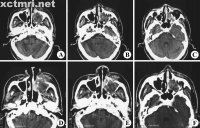

4.X线摄片示上颌窦腔密度增高、软组织肿块影及窦壁骨质破坏

4)眼部症状:突眼、流泪,结合膜充血,视力障碍复视。当窦内肿瘤向上扩展至眼眶时,可出现突眼、眼向上向前移位、结合膜充血、流泪。甚则眼球运动受限,继而出现视力障碍,眼球上视时有复视。

详细检查前后鼻腔,大多数病例有鼻腔异常,鼻腔外侧壁内移致鼻总道狭窄。当瘤侵入鼻腔时可通过前鼻孔或后鼻腔检查直接窥见。瘤体位于鼻腔侧壁或顶壁,呈灰红色,表面粗糙;或呈烂肉状,触之易出血;有时表面覆有污秽灰膜,伴组织坏死。鼻中道或鼻下道可见血性分泌物或血痂,或见鼻息肉样肿块,实为恶性肿瘤。因息肉样变与鼻息肉可与上颌窦肿瘤并存。因此,体格检查往往可早期发现异常表现,若鼻腔检查无特殊,也不能完全除外上颌窦恶性肿瘤,只要有临床症状,则宜作进一步检查。